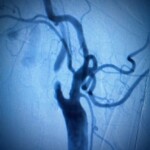

Diagnosing Carotid Disease

Your vascular provider will evaluate your medical and family history. Then they will do a thorough physical exam. If needed, a vascular ultrasound that we do in the office can confirm the presence and the severity of the disease.

Depending on the severity of your condition, treatment options may include lifestyle changes, medications, or procedures such as carotid endarterectomy or carotid artery stenting. Vascular surgeons use two approaches to carotid artery surgery. The procedures are similar, but having both options enables your surgeon to choose the one that meets your particular needs.

Transcarotid Arterial Revascularization (TCAR)

Some patients also benefit from a newer, minimally invasive procedure producing excellent results and outcomes called TCAR.

TCAR is the placement of a stent across the area of stenosis. Although it requires a small incision in the neck, the recovery is faster with less pain and scarring then CEA.

TCAR takes place in an operating room. After you’re placed under anesthesia, the surgeon makes a small incision in your neck, just above the collarbone. A tube is placed directly into your carotid artery and then connected to a system that temporarily reverses blood flow away from the brain; this prevents any loose bits of plaque from reaching the brain and causing a stroke. (Your brain still receives adequate blood from other arteries.) The blood is filtered by the system and then returned to your body through a second tube connected to a vein in your groin. While the blood flow is reversed, a stent (a small, expandable tube) is inserted into the artery to stabilize the plaque and prevent it from causing strokes. After the stent is in place, the surgeon halts the blood flow reversal and your blood resumes flowing toward the brain.